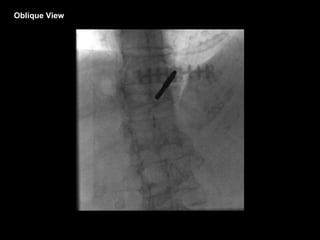

Oblique View